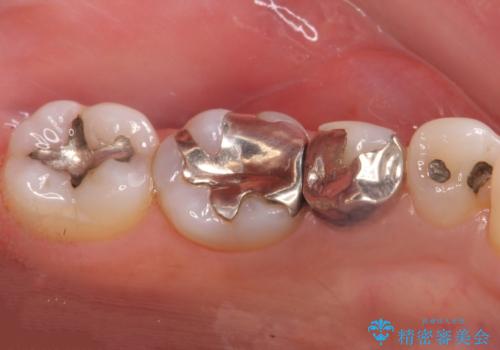

- 左下の奥歯に虫歯がある気がするとのことで来院された患者様です。

手前はジルコニアクラウンで白く、奥はゴールドアンレーでより適合の良いものを装着します。

銀歯の裏側に虫歯が確認されました。

小さな段差も虫歯のリスクにつながります。

精度の良い補綴物を入れることで今後の虫歯リスクを抑えることができます。